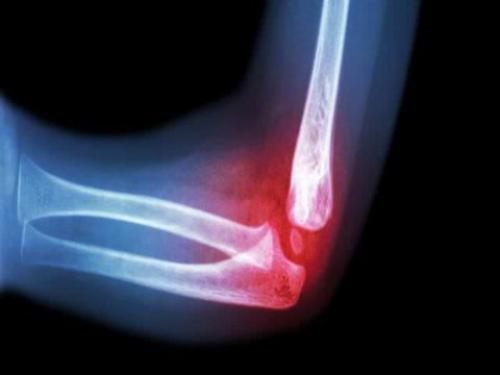

Перелом локтя

Травма с образованием трещины напоминает сильный ушиб, поэтому следует обязательно проконсультироваться у врача.

Сложной травмой локтевого сустава является его перелом.

Медики различают закрытый перелом без смещения, когда образуется трещина в локтевом суставе, со смещением и открытый, при котором раздробленные костные отломки образуют рану. Чаще всего ломается локтевой отросток Травме предшествуют следующие факторы:

Диагностические методы

Рентген позволит специалисту определить точный диагноз и методы лечения.

Травму локтя диагностирует травматолог или хирург-ортопед. Врач выясняет обстоятельства получения травмирования, проводит визуальный осмотр, прощупывает, определяя состояние кости и назначает рентгенографию. С помощью процедуры устанавливается присутствие или отсутствиеи вывиха, степень повреждения мягких тканей. Если результатов рентгена недостаточно, рекомендуется пройти артроскопию, УЗИ, КТ или МРТ.